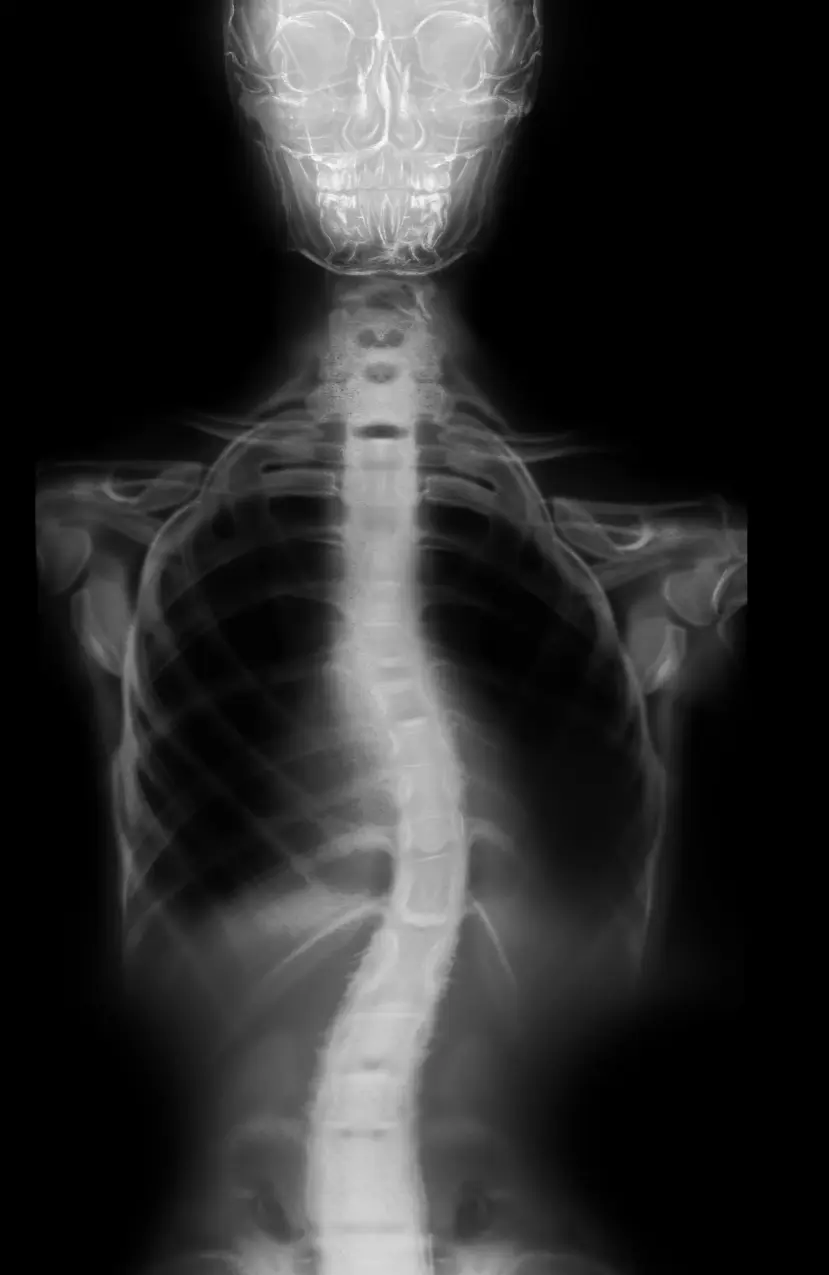

Antes